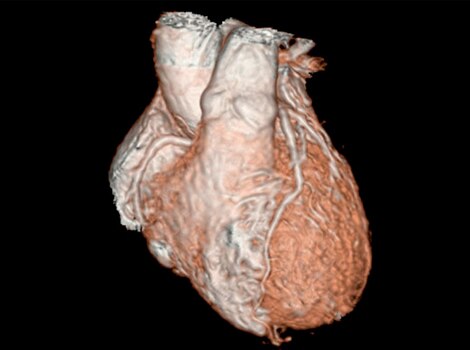

Revolution CT & CardioGraphe4

Achieve one-beat, whole heart acquisition for imaging or comprehensive cardiac assessment with or without beta blockers at any heart rate.5

Read More

Revolution CT & CardioGraphe7

Achieve one-beat, whole heart acquisition for imaging or comprehensive cardiac assessment with or without beta blockers at any heart rate.8

Revolution CT & CardioGraphe3

Achieve one-beat, whole heart acquisition for imaging or comprehensive cardiac assessment with or without beta blockers at any heart rate.4 Read More

Achieve one-beat, whole heart acquisition for imaging or comprehensive cardiac assessment with or without beta blockers at any heart rate.4